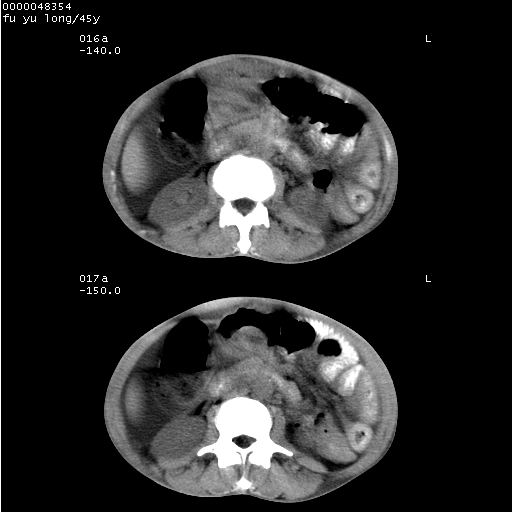

以下是引用医影拾贝在2008-5-30 2:38:00的发言:[br]气肿性胃炎、胃十二指肠溃疡、腹膜炎,考虑穿孔可能性较大

以下是引用lkc8963在2008-5-30 8:44:00的发言:[br]胃窦癌伴网膜(胃结肠韧带)/腹膜及腹膜后淋巴结转移.